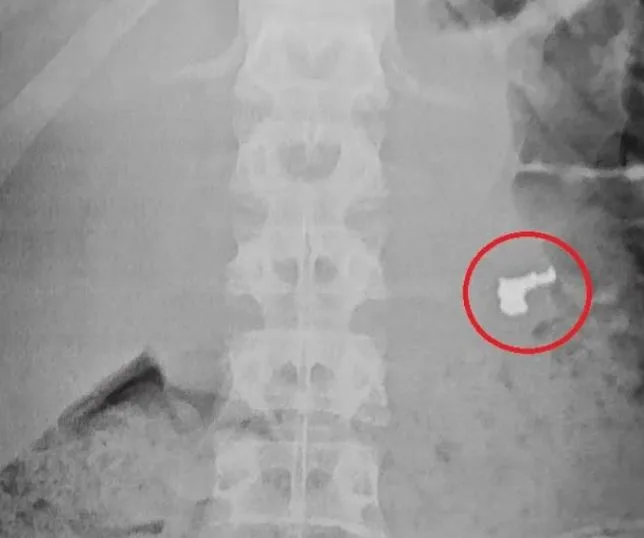

Na unidade de saúde foram realizados exames de raios X , sendo que o resultado de um deles identificou a joia roubada. Os três menores foram encaminhados à Delegacia Sede de Guarujá, onde a ocorrência foi registrada.